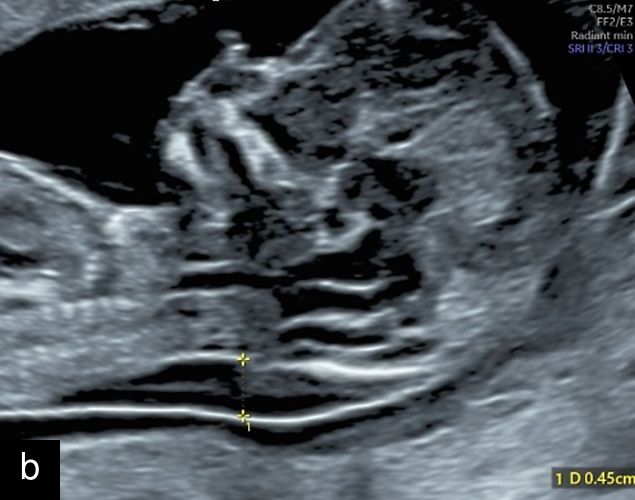

7

(a) Congenital diaphragmatic hernia at 13 weeks with a four-chamber view of the heart (in color) with mediastinal shift and stomach visible in left hemithorax. (b) Congenital diaphragmatic hernia at 20 weeks with a four-chamber view of the heart with the small left ventricle and mediastinal shift, and stomach visible in left hemithorax.